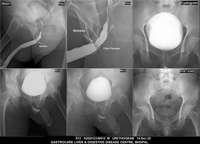

Section: URETHROGRAM

Total: 95 Cases